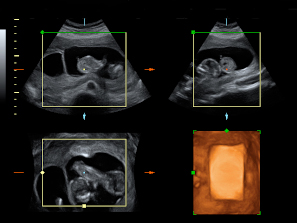

El bienestar fetal de este bebé de 11 semanas de gestación parece evidente a juzgar por su movimiento de brazos y piernas. Esta ecografía 4D ofrece el "baile" de este pequeñín, que está finalizando su primer trimestre de embarazo.

Ecografía en 4D de feto de 11 semanas moviéndose

Feto de 11 semanas de gestación con brazos y piernas en movimiento continuo dentro del útero materno. No se aprecian las extremidades con nitidez debido al "corte" de imagen que selecciona el ecografista.